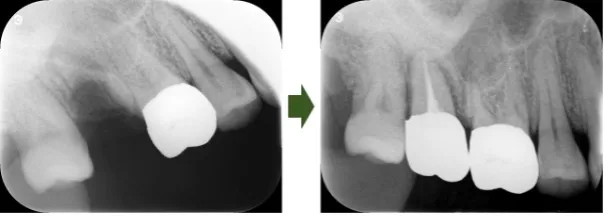

歯の移植

抜歯後の歯の喪失は、入れ歯やブリッジ、インプラント、歯の移植などで対応することが可能です。場合によっては、歯の移植は保険で実施できることがあります。詳細については歯科医師にご相談ください。

抜歯した親知らずで歯の喪失を補った例をご紹介します。

手術後2年以上が経過しておりますが、特に問題はございません。